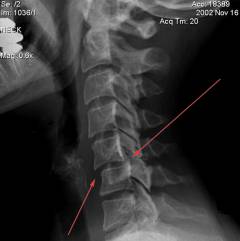

Рентгенологическое исследование

Для уточнения диагноза и выявления костных патологий проводят рентгенографию. На снимках могут быть аномалии шейных позвонков, такие как дополнительный клиновидный позвонок или деформация.

Для уточнения диагноза и выявления костных аномалий выполняются рентгеновские снимки.

На рентгенограммах могут быть обнаружены аномалии шейных позвонков, такие как дополнительный клиновидный позвонок или деформации. Также возможно частичное сращение шейных позвонков, что приводит к кривошее.